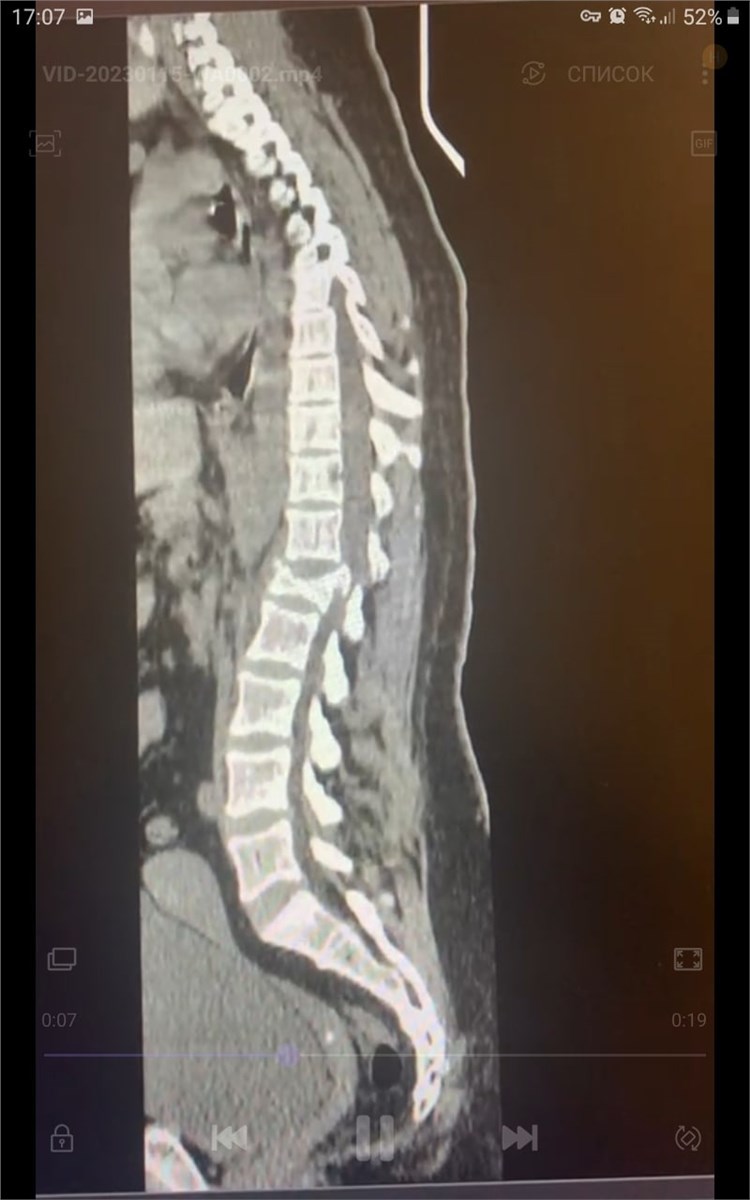

В Красноярске врачи БСМП прооперировали молодую женщину, которая получила серьезную травму позвоночника во время спуска с горы на тюбинге.

В  Красноярске врачи БСМП прооперировали молодую женщину, которая получила серьезную травму позвоночника во  время спуска с  горы на  тюбинге. Пострадавшая на  скорости выпала из  «плюшки».

Оперативное лечение женщины проходило в  несколько этапов. Травматологи в  месте травмы зафиксировали позвонки при помощи специальных имплантов

«Ежегодно мы  сталкиваемся с  такими пострадавшими,  — рассказывает заведующий отделением травматологии красноярской БСМП Константин Тутынин. —  Травмы очень серьезные, они требуют многочасовых операций, а  порой и  нескольких операций, затем пациенты проходят длительную реабилитацию и  восстановление. Таким образом лечение растягивается на  несколько месяцев, и  это в  лучшем случае. Были пациенты, которые поступали с  тяжелыми травмами позвоночника, где был поврежден спинной мозг  — развлечение закончилось инвалидностью».